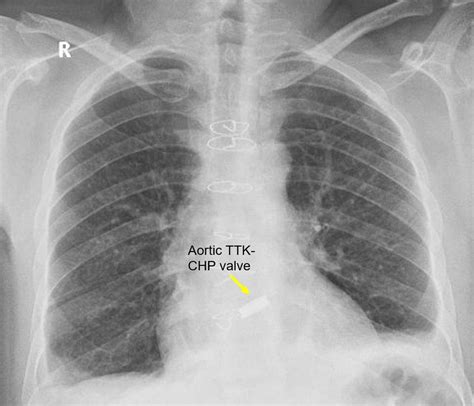

David Buttars Blog